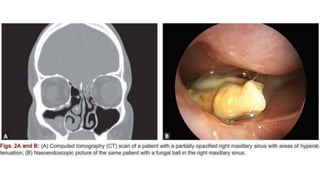

2. Fungal ball

• Dense accumulation of extramucosal fungal hyphae usually within one sinus

Most common

Sinus: Maxillary

Organism: Aspergillus

Immunocompetant,middle

aged and elderly females with

h/o previous dental procedure

Diagnosis

• Non specific chronic inflammation of the sinus in the

absence of eosinophil predominance, granuloma and

allergic mucin

• Microscopy: Accumulation of fungal hyphae without

evidence of tissue fungal invasion

• Radiology: Sinus opacification with areas of hyper

attenuation, cheesy or clay like debri within the sinus